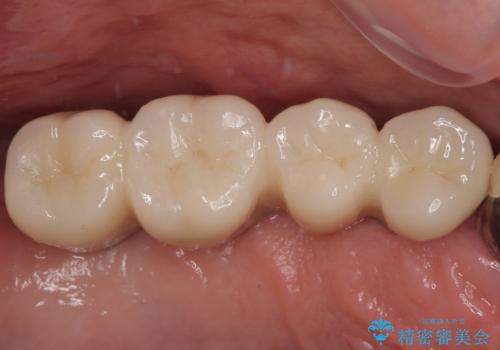

奥歯の大きなむし歯 神経を残してセラミック治療